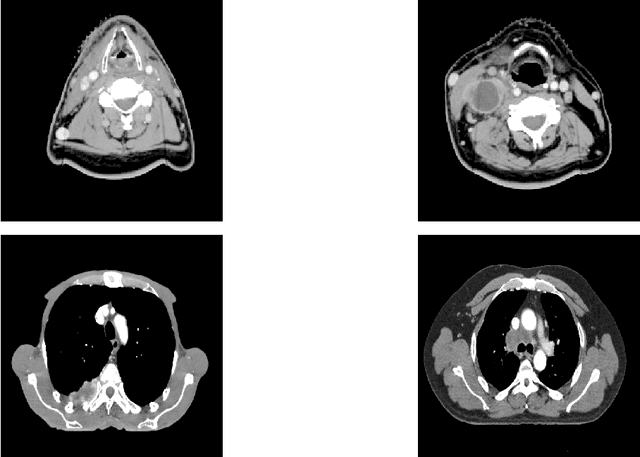

Abstract:In this paper, we propose to quantitatively compare loss functions based on parameterized Tsallis-Havrda-Charvat entropy and classical Shannon entropy for the training of a deep network in the case of small datasets which are usually encountered in medical applications. Shannon cross-entropy is widely used as a loss function for most neural networks applied to the segmentation, classification and detection of images. Shannon entropy is a particular case of Tsallis-Havrda-Charvat entropy. In this work, we compare these two entropies through a medical application for predicting recurrence in patients with head-neck and lung cancers after treatment. Based on both CT images and patient information, a multitask deep neural network is proposed to perform a recurrence prediction task using cross-entropy as a loss function and an image reconstruction task. Tsallis-Havrda-Charvat cross-entropy is a parameterized cross entropy with the parameter $\alpha$. Shannon entropy is a particular case of Tsallis-Havrda-Charvat entropy for $\alpha$ = 1. The influence of this parameter on the final prediction results is studied. In this paper, the experiments are conducted on two datasets including in total 580 patients, of whom 434 suffered from head-neck cancers and 146 from lung cancers. The results show that Tsallis-Havrda-Charvat entropy can achieve better performance in terms of prediction accuracy with some values of $\alpha$.